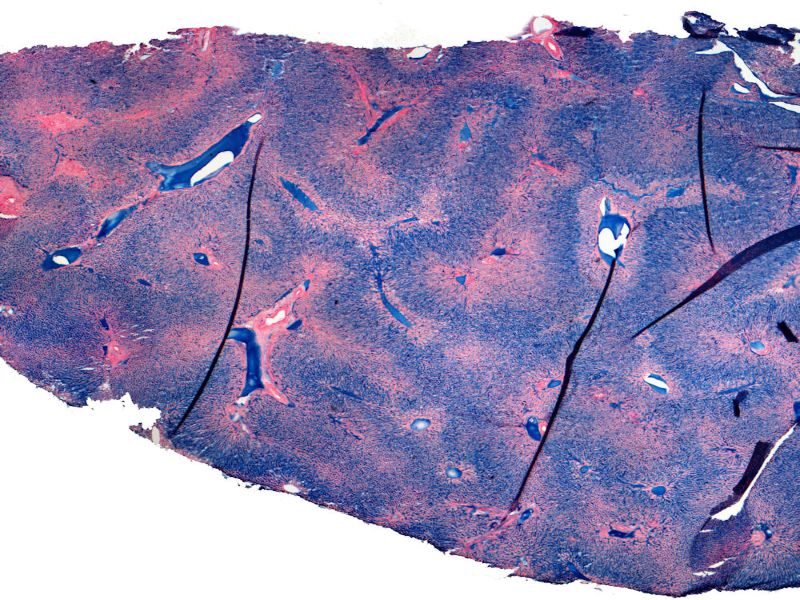

Metabolism: Liver